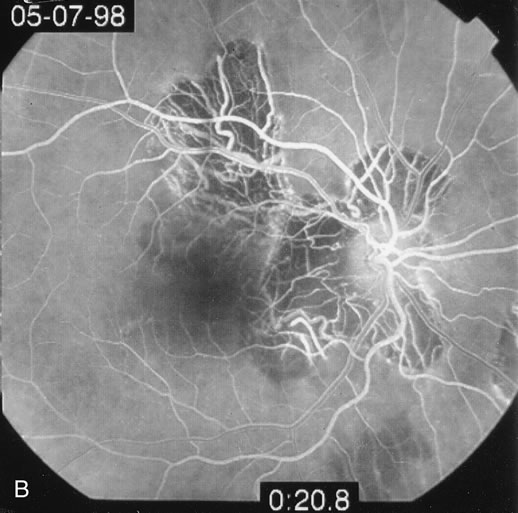

The classic findings in the acute cases are lesions of variable size that are hypofluorescent in the early phase of the fluorescein angiogram. In the late phases of the angiogram there is hyperfluorescence of the lesions. In the late phases, there also may be leakage from the disc as well, and there also may be staining of the retinal vessels because of the vasculitis. With resolution of the disease, there still may be a mottled pattern of fluorescence correlating with the areas of pigment clumping and pigment atrophy (Fig. 8).

Fig. 8. A. Early fundus angiogram showing hypofluorescence of the acute posterior multifocal placoid pigment epitheliopathy (APMPPE) lesions. B. Later stage of the angiogram showing staining of the APMPPE lesions.

Fig. 16. A. Color fundus photograph showing the jigsaw pattern of choroidal and retinal atrophy extending from the disc along the arcades. At the inferior edge of the superotemporal lesion there is a recurrence noted by the grayness of the retina. B. Fluorescein angiogram in the laminar venous phase showing a large window defect in the area of inactive choroiditis and blockage of the choroidal fluorescence in the area of active choroiditis. C. In the late phase of the fluorescein angiogram there is staining of the edges of the inactive choroiditis and marked hyperfluorescence in the area of active choroiditis.

Fig. 17. A. Classic inactive case of serpiginous choroiditis showing the jigsaw pattern of disease surrounding the fovea. B. Fluorescein angiogram showing staining of the edges of the inactive serpiginous choroiditis. There is blocked fluorescence in the areas of hyperplasia of the retinal pigment epithelium. C. Indocyanine green angiogram showing absence of fluorescence in the area of inactive choroiditis.